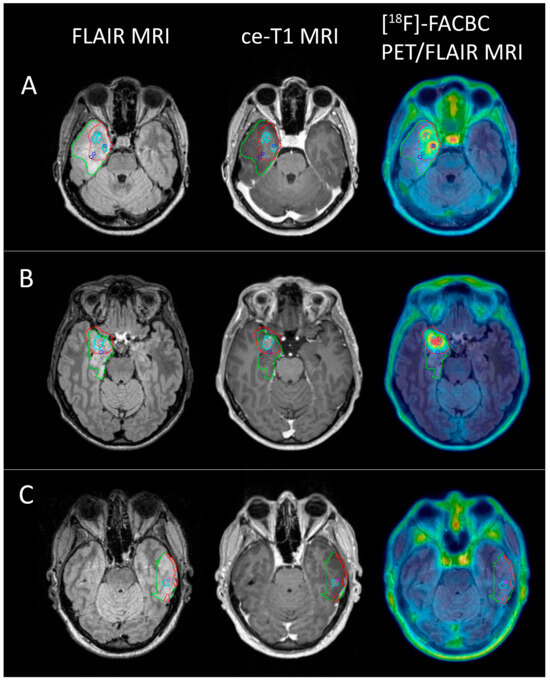

Histomolecular Validation of [18F]-FACBC in Gliomas Using Image-Localized Biopsies

Background: Gliomas have a heterogeneous nature, and identifying the most aggressive parts of the tumor and defining tumor borders are important for histomolecular diagnosis, surgical resection, and radiation therapy planning. This study evaluated [18F]-FACBC PET for glioma tissue classification. Methods: Pre-surgical [...] Read more.

Background: Gliomas have a heterogeneous nature, and identifying the most aggressive parts of the tumor and defining tumor borders are important for histomolecular diagnosis, surgical resection, and radiation therapy planning. This study evaluated [18F]-FACBC PET for glioma tissue classification. Methods: Pre-surgical [18F]-FACBC PET/MR images were used during surgery and image-localized biopsy sampling in patients with high- and low-grade glioma. TBR was compared to histomolecular results to determine optimal threshold values, sensitivity, specificity, and AUC values for the classification of tumor tissue. Additionally, PET volumes were determined in patients with glioblastoma based on the optimal threshold. [18F]-FACBC PET volumes and diagnostic accuracy were compared to ce-T1 MRI. In total, 48 biopsies from 17 patients were analyzed. Results: [18F]-FACBC had low uptake in non-glioblastoma tumors, but overall higher sensitivity and specificity for the classification of tumor tissue (0.63 and 0.57) than ce-T1 MRI (0.24 and 0.43). Additionally, [18F]-FACBC TBR was an excellent classifier for IDH1-wildtype tumor tissue (AUC: 0.83, 95% CI: 0.71–0.96). In glioblastoma patients, PET tumor volumes were on average eight times larger than ce-T1 MRI volumes and included 87.5% of tumor-positive biopsies compared to 31.5% for ce-T1 MRI. Conclusion: The addition of [18F]-FACBC PET to conventional MRI could improve tumor classification and volume delineation. Full article

Show Figures

Figure 1